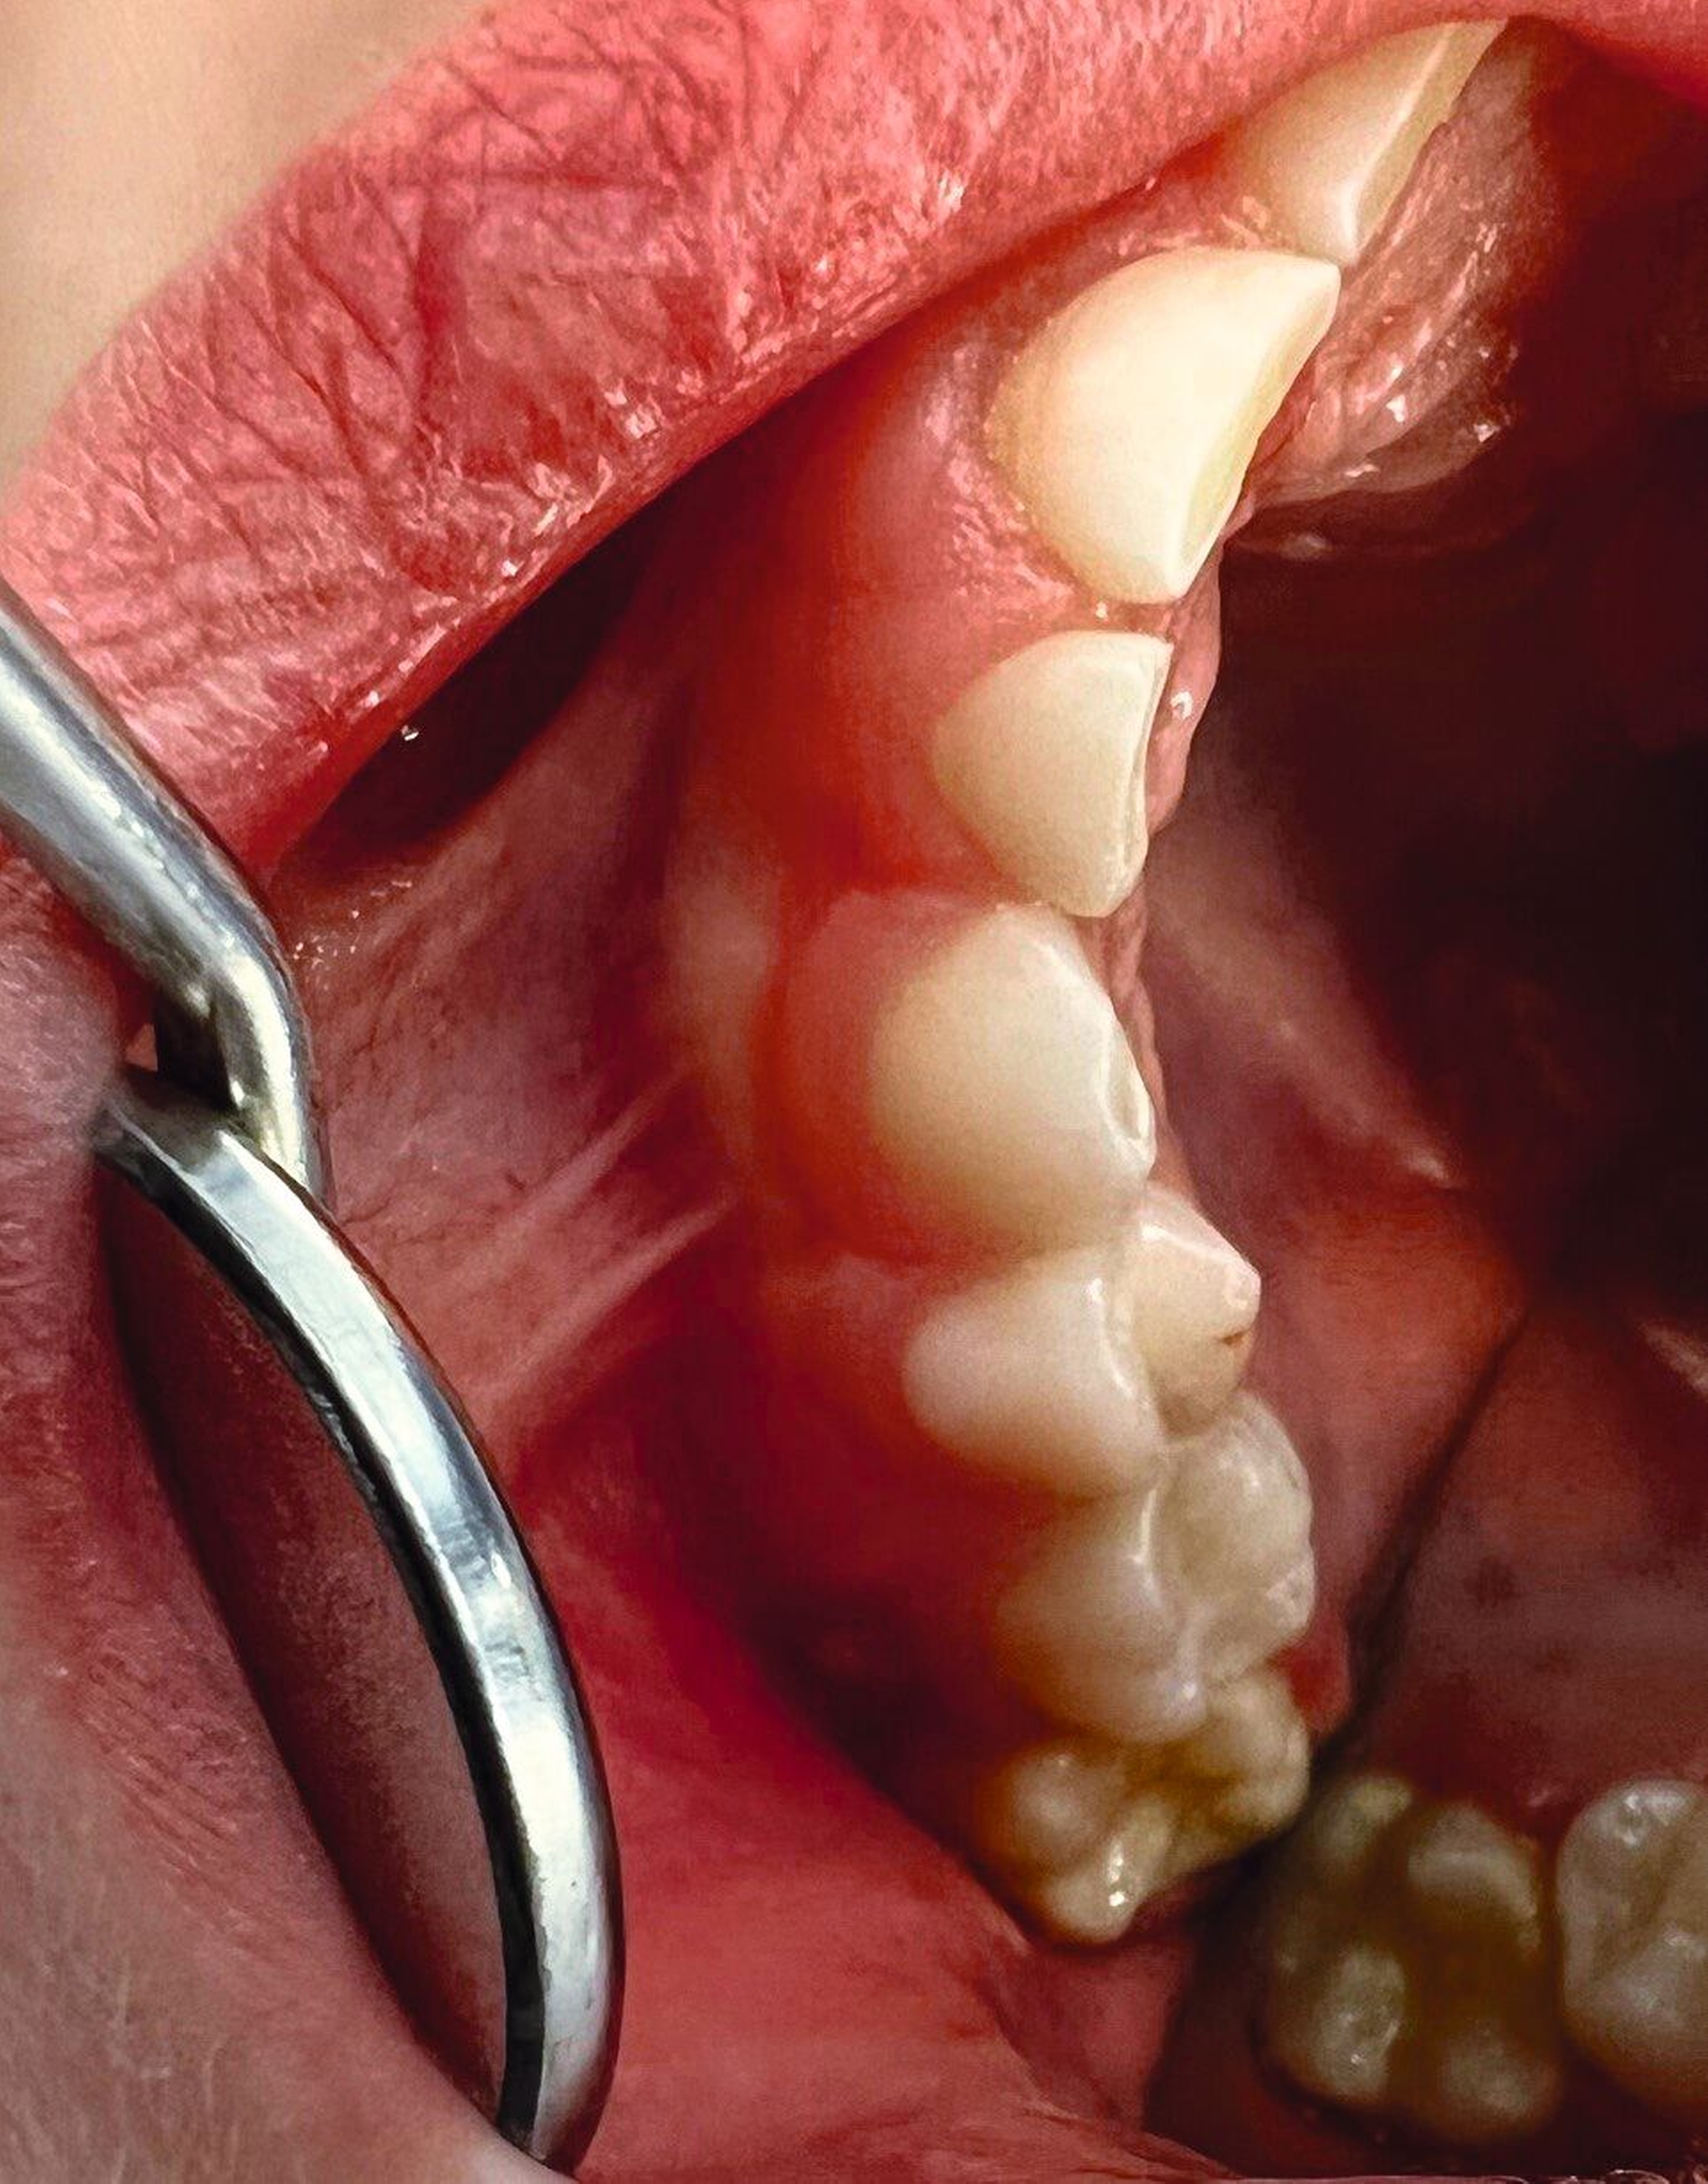

Wenn der Patient nach dem Schlafen über Beschwerden in der Kaumuskulatur oder Beeinträchtigungen im täglichen Leben klagt, handelt es sich um eine schwerwiegende statische Form. Über die Beurteilung der Schlifffacetten an den Front- und Seitenzähnen wird die Diagnose der dynamischen Form erhoben. Diese kann entweder an Studienmodellen oder direkt im Mund erfolgen. Der Schweregrad der Attritionen reicht von der alleinigen Schmelz- bis zur Pulpabeteiligung. Schließlich muss man Zahnhartsubstanzverlust, der bis ins Dentin reicht, bei Kindern und Jugendlichen als schwere Form des Bruxismus bewerten, da die Zähne vergleichsweise kurz in der Mundhöhle sind (Abbildungen 3 und 4).